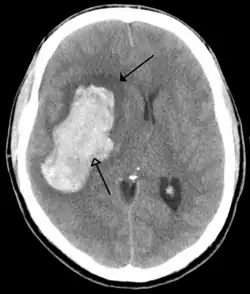

The brain is protected by the skull, suspended in cerebrospinal fluid, and isolated from the bloodstream by the blood–brain barrier. However, the brain is still susceptible to damage, disease, and infection. Damage can be caused by trauma, or a loss of blood supply known as a stroke. The brain is susceptible to degenerative disorders, such as Parkinson's disease, dementias including Alzheimer's disease, and multiple sclerosis. Psychiatric conditions, including schizophrenia and clinical depression, are thought to be associated with brain dysfunctions. The brain can also be the site of tumours, both benign and malignant; these mostly originate from other sites in the body.

Tumours

Brain tumours can be either benign or cancerous. Most malignant tumours arise from another part of the body, most commonly from the lung, breast and skin.[178] Cancers of brain tissue can also occur, and originate from any tissue in and around the brain. Meningioma, cancer of the meninges around the brain, is more common than cancers of brain tissue.[178] Cancers within the brain may cause symptoms related to their size or position, with symptoms including headache and nausea, or the gradual development of focal symptoms such as gradual difficulty seeing, swallowing, talking, or as a change of mood.[178] Cancers are in general investigated through the use of CT scans and MRI scans. A variety of other tests including blood tests and lumbar puncture may be used to investigate for the cause of the cancer and evaluate the type and stage of the cancer.[178] The corticosteroid dexamethasone is often given to decrease the swelling of brain tissue around a tumour. Surgery may be considered, however given the complex nature of many tumours or based on tumour stage or type, radiotherapy or chemotherapy may be considered more suitable.[178]

Some treatments for stroke are time-critical. These include clot dissolution or surgical removal of a clot for ischaemic strokes, and decompression for haemorrhagic strokes.[196][197] As stroke is time critical,[198] hospitals and even pre-hospital care of stroke involves expedited investigations – usually a CT scan to investigate for a haemorrhagic stroke and a CT or MR angiogram to evaluate arteries that supply the brain.[195] MRI scans, not as widely available, may be able to demonstrate the affected area of the brain more accurately, particularly with ischaemic stroke.[195]